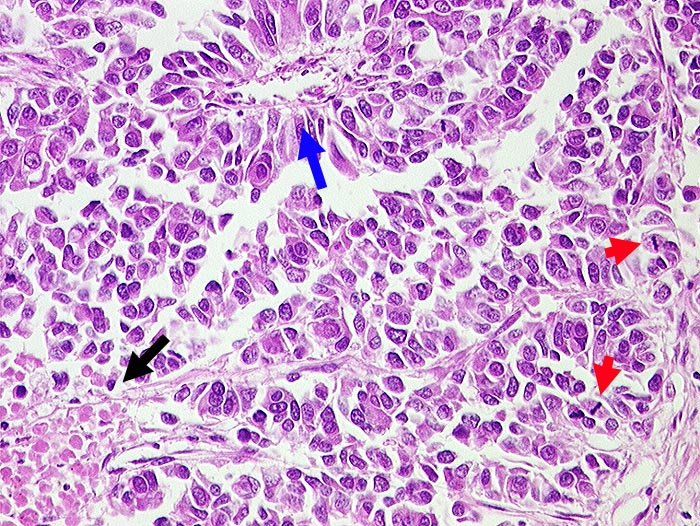

Grosszelliges neuroendokrines Karzinom

Lunge

Mittelgrosse Tumorzellen mit reichlich Zytoplasma und zahlreichen Mitosen. Herdförmige Nekrosen. Pseudorosettenbildung um Gefäss.

Zentrales Bronchuskarzinom. Synaptophysin und NSE positiv.